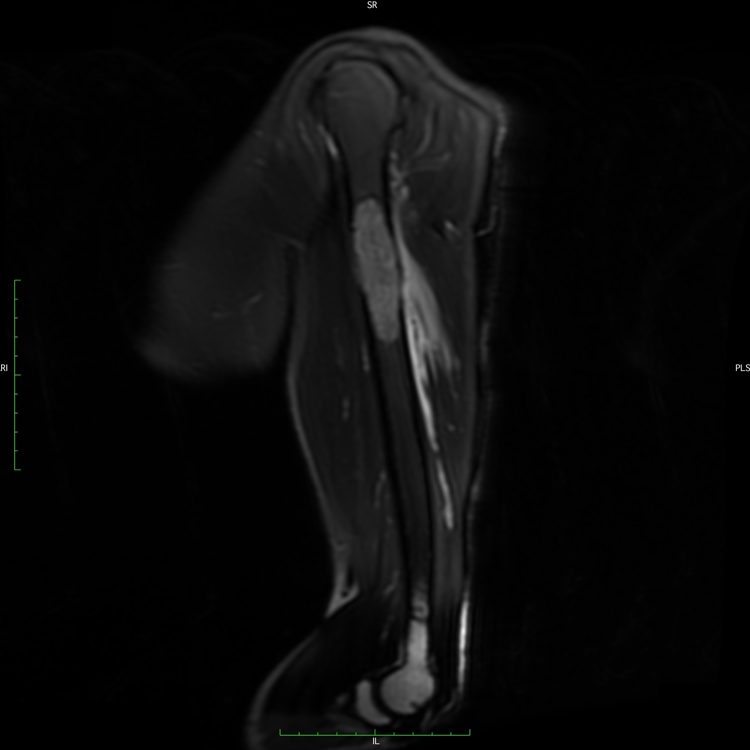

MRI of Myeloma

This is an MRI of Myeloma. Advanced imaging such as MRI, or magnetic resonance imaging, is used to help diagnose the disease and show the extent of the disease.